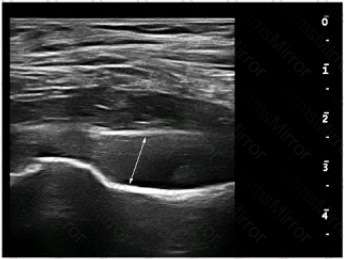

What is the MAXIMUM normal dimension of the structure indicated by the line in this image?